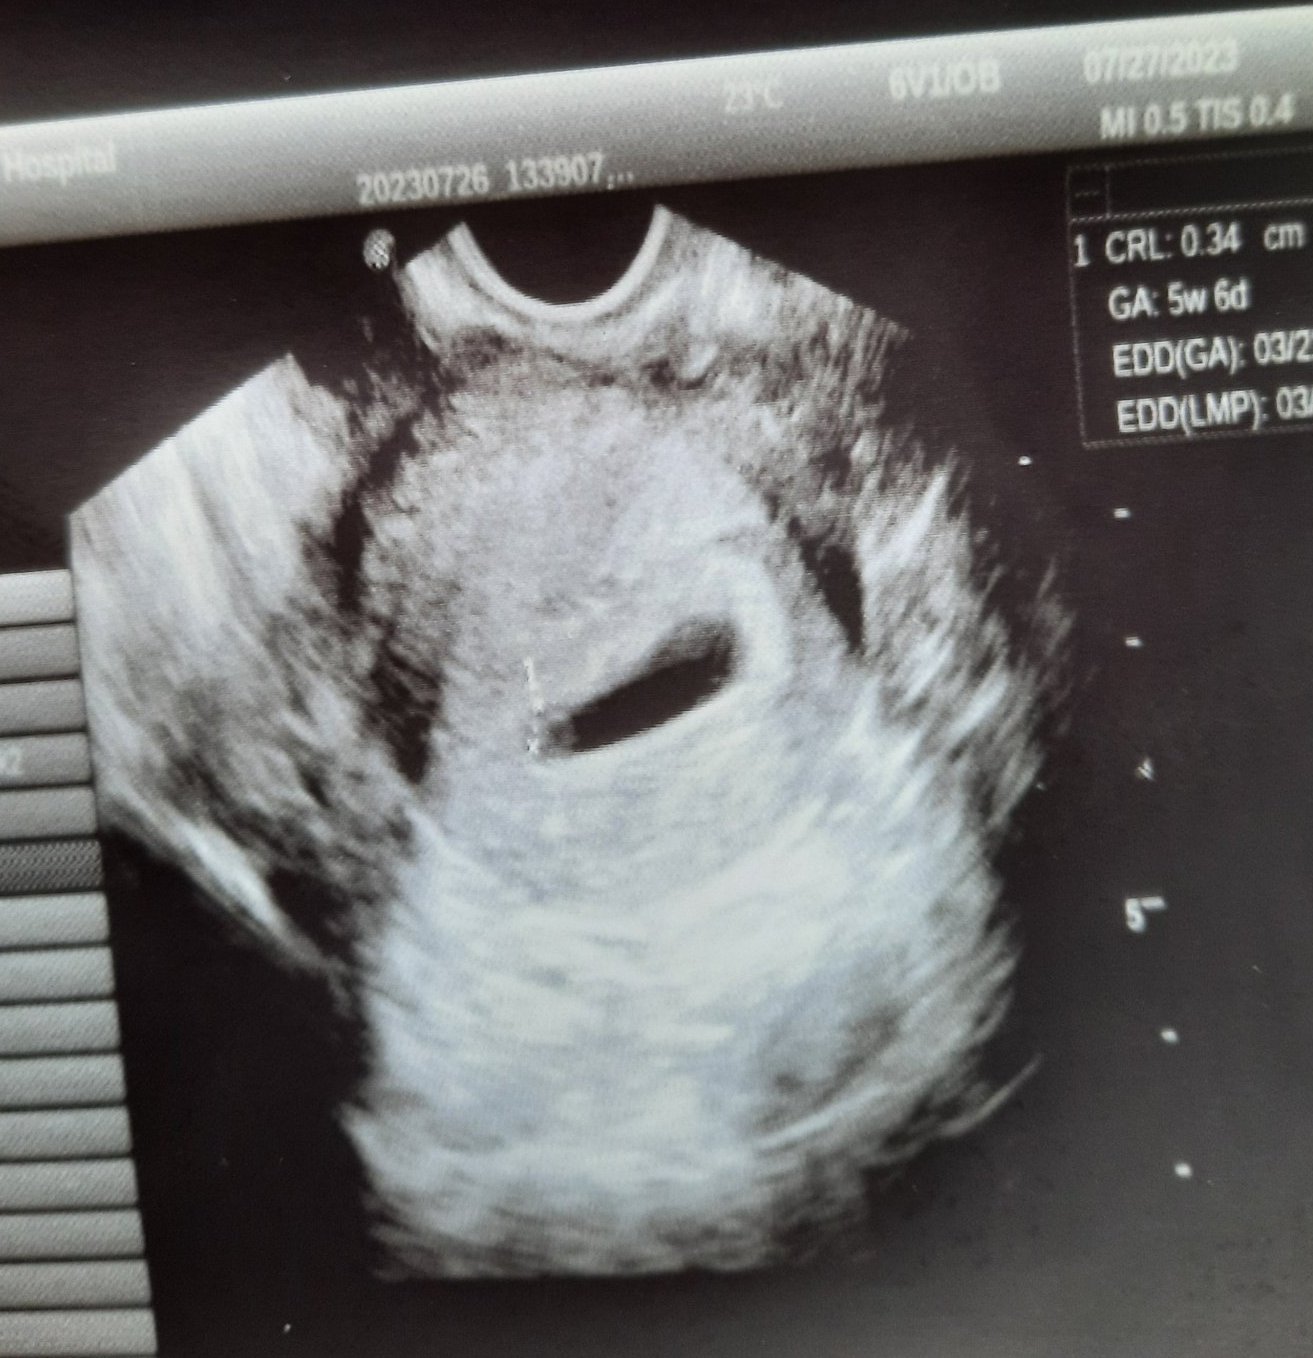

Здравейте. Току-що бях на преглед и искам да споделя с вас огромното си щасте. Имам си вече ембрионче 0,34см, отговарящо на 5г.с и 6 дни, при аменорея 6 г.с, което докторът каза, че е наред, за 1 ден разлика нямало какво да се притеснявам, нищо не било. Най-важното е, че видя сърдечни пулсации, което е нещото, за което си мечтая да чуя от година вече(с първята бременност така и не чух това изречение, нищо че ембриона беше вече 1,68см). И от 14ти август вече минавам по направление номер 34.8, тоест наблюдение при нормално протичаща бременност.

Буквално летя. Голяма част от страховете ми се стопиха, дори така както ме болеше корема ниско долу отведнъж спря.